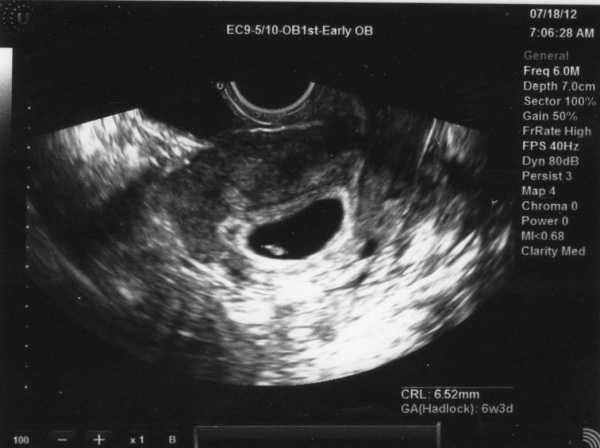

УЗИ

В начале четвёртой акушерской недели исследование вряд чем-то поможет. Зато в конце на качественном оборудовании хороший специалист уже кое-что разглядит. Это будет матка с толстым слоем эндометрия и эмбрион – маленькая чёрная точка. Если у женщины ранее была внематочная беременность, врач-специалист обязательно проверит всю женскую систему.

Фото плода, УЗИ

Эти исследования заключаются, в основном, в назначении врачом анализа на ХГЧ, который подтверждает беременность. Крайне редко делают УЗИ на четвертой неделе беременности, которое может показать желтое тело, определить в матке наличие зародыша. Чаще всего на этом сроке женщины не обращаются к врачу, так как могут и не подозревать о своем положении, а тесты, к сожалению, не всегда ее определяют.

Откажитесь или ограничьте количество сладостей, полуфабрикатов, консервов, копченых, жирных и соленых продуктов. Не стоит есть продукты с ароматизаторами, красителями и пищевыми добавками. Отдайте предпочтение мясным, молочным, злаковым блюдам, а также свежим овощам и фруктам. Отдайте предпочтение мясным, молочным, злаковым блюдам, а также свежим овощам и фруктам. Стоит также позаботиться и о своем здоровье. Поэтому настоятельно рекомендуем вам почитать статью, о том, как повысить гемоглобин при беременности. За более детальной консультацией все же советуем обратиться к своему врачу. Здоровья вам и вашему малышу! Следуя этим советам вы легко справитесь с таким нелегким состоянием: Также старайтесь больше отдыхать и заряжаться позитивными эмоциями, вам и вашему малышу нужны светлые и приятные мысли. Поверьте, время пролетит очень быстро, а с ним и неприятные ощущения. Так, за 4 последует 5, за ней 6 неделя беременности, ощущения в животе при которой оставляют желать лучшего. Еще немного времени – и вот уже 11 неделя беременности, а спустя пол года – роды. Главное – получать только положительные эмоции! Вы наверняка найдете интересными следующие фото УЗИ на 4 недели беременности. УЗИ на 4 неделе беременности Плохая видимость плода на 4 неделю А на этом снимке видна двойня Так выглядит распечатанный снимок УЗИ Стрелочками указано расположение плода 4 неделя беременности, исследование хорионического гонадотропина Этот сюжет посвящен симптомам и признакам 4 недели беременности, о которых детально расскажет врач-акушер. А это видео рассказывает об опасностях, которые поджидают будущих мам на 3 и 4 неделе беременности. Читайте также:

На 4 неделе беременности ультразвуковое исследование может показать только жёлтое тело, которое играет главную роль – обеспечение эмбриона всеми необходимыми питательными веществами до того времени, пока процесс формирования плаценты не закончится. Именно жёлтое тело вырабатывает гормон прогестерон, который отвечает за сохранение беременности. Ультразвуковое исследование на 4 неделе беременности с уверенностью покажет вам, прикрепился ли эмбрион в полости матки или нет. А вот проведение обследования на столь маленьком сроке делается очень редко, ведь на этом этапе женщина только начинает подозревать, что беременна.

Обследование на УЗИ

Ультразвуковое обследование на 4 неделе позволяет обнаружить растущее жёлтое тело, размеры которого могут намекнуть, что имплантация плодного яйца произошла. При использовании высокочувствительного аппарат УЗИ возможно обнаружение самого зародыша. Но проводить такое исследование на столь ранних сроках не рекомендуется, так как это может негативно сказаться на развитии эмбриона.

Сейчас быстро увеличивается головной мозг, и растет голова. Если посмотреть на снимки УЗИ на 4 неделе беременности, то можно разглядеть места зачатков ручек и ножек, лица, ротовой полости.

На фото УЗИ на 4 неделе акушерской беременности будущий малыш выглядит как малюсенькая точка – зернышко мака.

УЗИ на 4 неделе беременности

Если аппарат ультразвукового исследования обладает высокими чувствительными характеристиками, то на 4 неделе беременности на снимках можно рассмотреть не только увеличившееся желтое тело, но и сам зародыш.

Стоит ли проводить УЗИ на столь раннем сроке, решит врач. Хотя вредное воздействие ультразвуковых волн на эмбрион или на саму беременную никак не доказано.